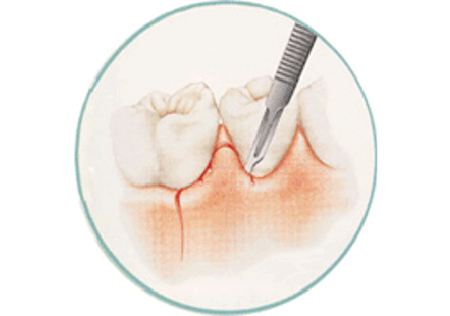

歯周外科治療

麻酔をして少し歯茎を開いてあげると、歯周病菌を目で見て除去することが可能になり、徹底的に歯周病菌を除去できます。また格段に歯周病治療の成績が向上します。条件が揃えば、失ってしまった骨を増やすような再生治療を行うことも可能です。